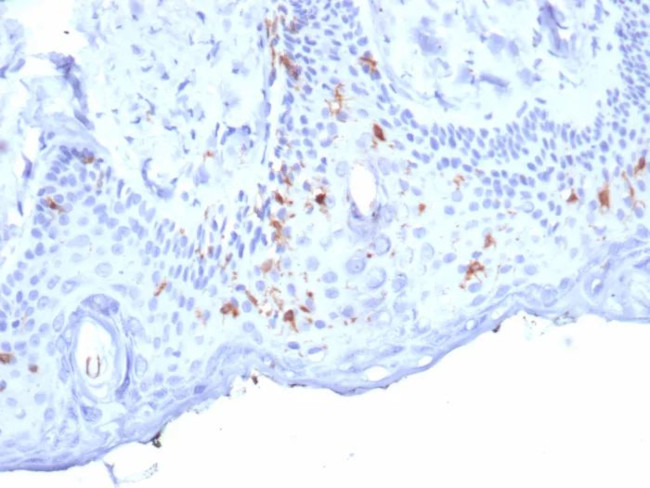

Langerin/CD207 (Marker of Langerhans Cells) Antibody in Immunohistochemistry (Paraffin) (IHC (P))

Langerin/CD207 (Marker of Langerhans Cells) Antibody (50489-MSM7-P1ABX) in IHC (P)

Formalin-fixed, paraffin-embedded human skin stained with Langerin Mouse Monoclonal Antibody (LGRN/7357). HIER: Tris/EDTA, pH9.0, 45 min. 2°C: HRP-polymer, 30 min. DAB, 5 min. {{ $ctrl.currentElement.advancedVerification.fullName }} 验证信息 View more

Positive Control:Human skin.

Cellular Location: Cell Surface. Cytoplasm.

Langerin (CD207) is a type II membrane-associated C-type lectin known to be expressed exclusively by Langerhans cells. Lamgerin recognizes mannose residues via its single carbohydrate recognition domain (CRD). Langerin is localized not only on the cell surface, but also intracellularly in close association with Birbeck granules. Transfection of Langerin cDNA into fibroblasts creates a compact network of membrane structures with typical features of Birbeck granules (BG). Langerin is thus a potent inducer of membrane superimposition and zippering leading to BG formation.